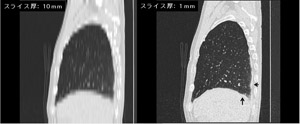

通常、アスベスト関連疾患の検診では、レントゲン写真・血液検査・問診などが用いられますが、やはりCTが胸部検診では有力だと思います。いまCTで標準的に採用されている画像は、スライス厚10mmのものが広く用いられます。ですが、これでは大きくなったもの、治癒が難しいものしか見つけられません。治療可能な部位を早期発見するためにはスライス厚1mmの高精度なCT検診が必要です。

スライス厚10mm、1mmの画像の解像度違いというのはどの程度のものなのでしょうか。

写真をみくらべると一目瞭然です。この画像はアスベスト関連疾患の症状の方の一例で、胸膜付近に異常の候補と思われる領域がありますが(矢印付近)、10mm厚の画像では、ぼやけて認知できません。やはり現場で実際に使える診断支援のCT画像であるならば、スライス厚1㎜が望ましいのです。

図 CT画像の比較(左:スライス厚10mm.右:スライス厚1mm)